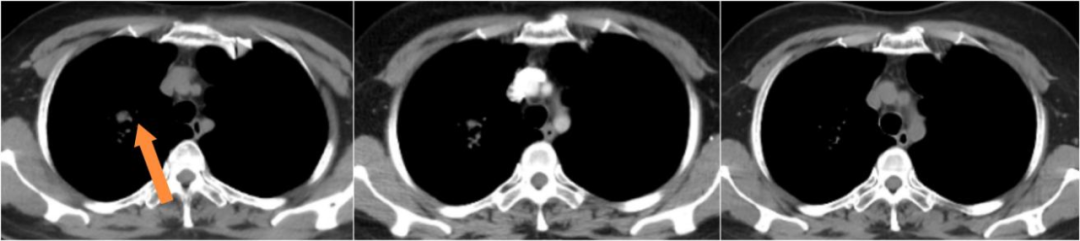

患者男,79岁,2025.5月以“右下肢无力1月”为主诉入院,检查头MRI+C:左侧额叶异常强化,周围片状水肿信号,符合转移瘤;肺CT+C:右肺上叶纵隔旁肿物,可疑恶性。行肺穿刺活检病理诊断为肺腺癌伴少数鳞状分化,免疫组化PD-L1(22C3)TPS=70%,基因检测:KRAS G12V突变,临床分期:cT2aN0M1b IVA期,PS评分1分。恰逢依沃西单抗单药获国家药品监督管理局批准于PD-L1表达阳性(PD-L1 TPS≥1%)的局部晚期或转移性非小细胞肺癌的一线治疗适应症,2025年6月行依沃西单抗单药治疗4周期后患者右下肢无力症状明显缓解,10月复查头增强MRI额叶周围水肿带消失,疗效评价持续PR,治疗期间出现不良反应为恶心呕吐II级,对症止吐治疗后好转,目前持续治疗中。

依沃西单抗4周期疗效对比